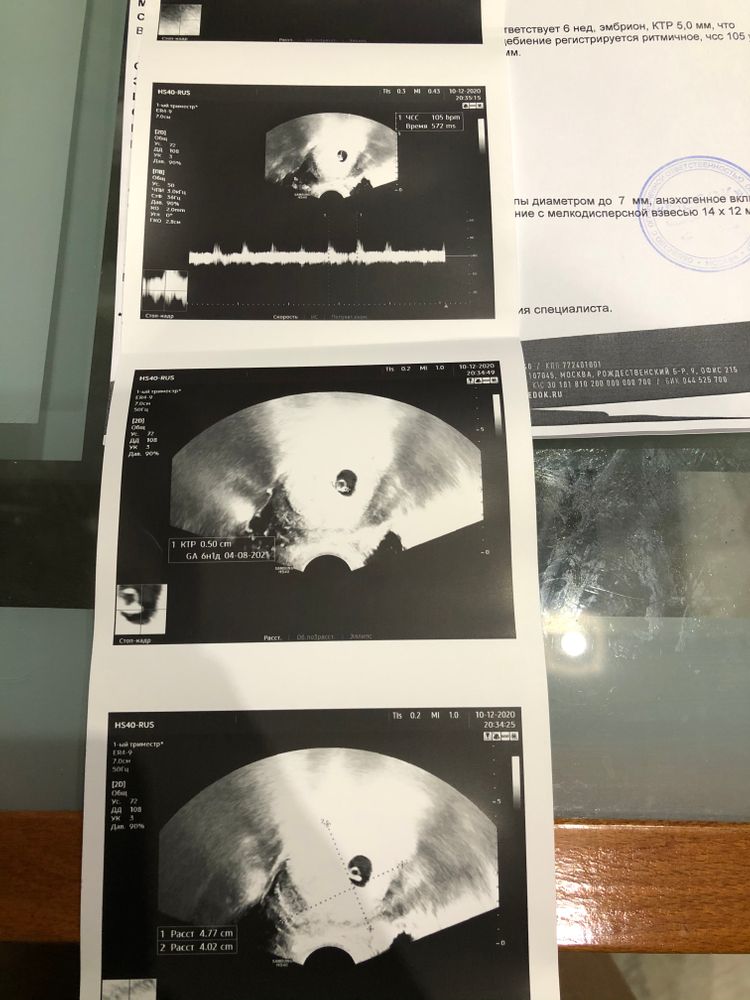

Узи 7-ая неделя! Услышали сердечко❤️